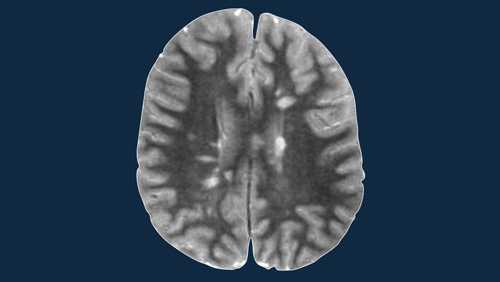

Multiple Sclerosis 2.0